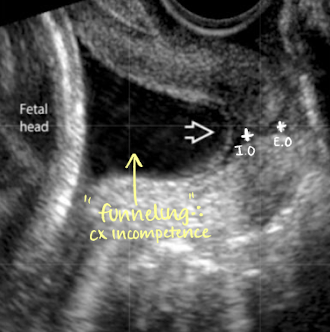

what is cervical incompetence

when CL is less than 2.5 cm

cervix does not remain closed

is this normal or cervical incompetence?

incompetence